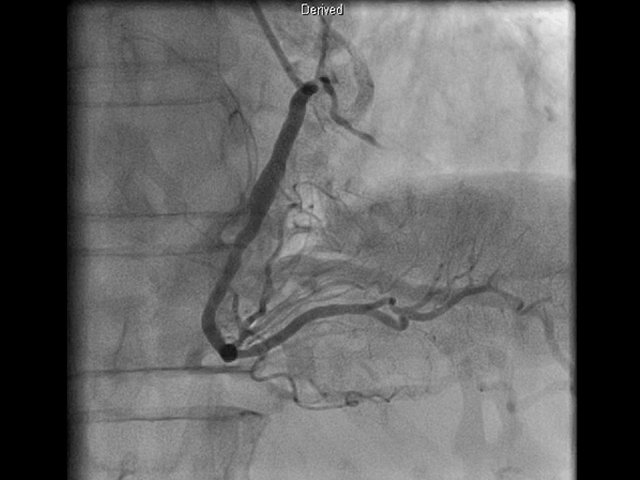

80 minutes Angiography Recorded on 24th Mar 2016 This webinar was a huge success. It will boost your understanding of how to read and interpret angiograms.